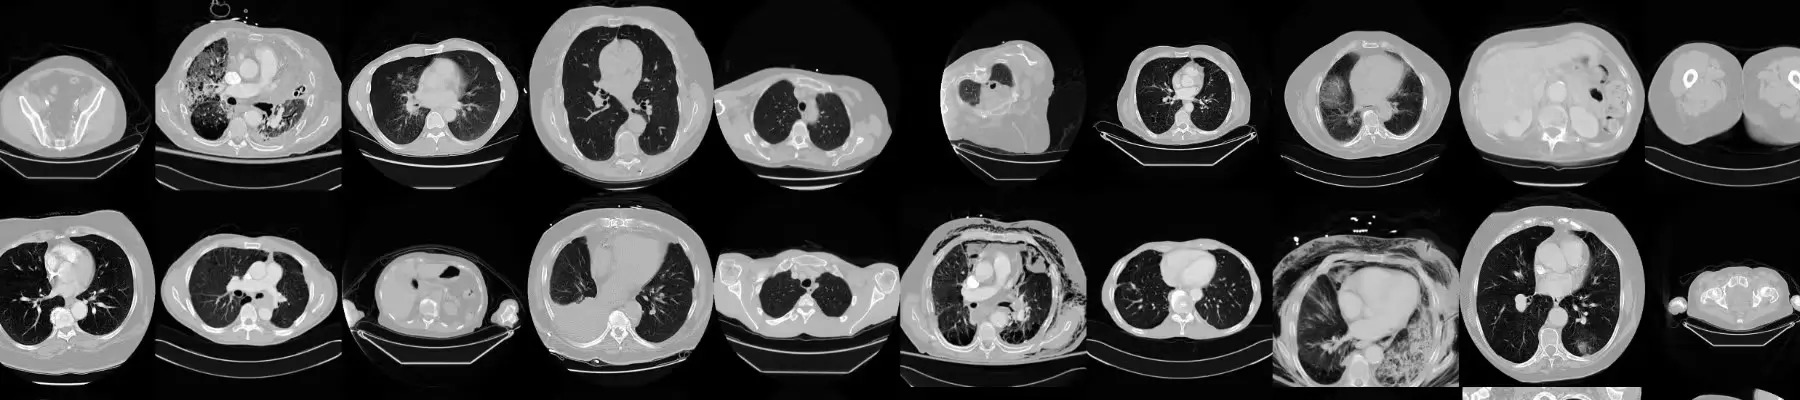

7. CT Medical Images

The CT Medical Image dataset is a small sample drawn from the Cancer Imaging Archive, specifically selected for meeting certain criteria regarding age, modality, and contrast tags.

This dataset is designed to train models that can recognize image textures, statistical patterns, and highly correlated features. This capability allows for the development of straightforward tools to automatically classify misclassified images and identify outliers. Such outliers might indicate suspicious cases, inaccurate measurements, or inadequately calibrated machines in cancer treatment.

- Focus: Medical Image Analysis

- Research Paper: The Cancer Genome Atlas Lung Adenocarcinoma Collection

- Author: Justin Kirby

- Dataset Size: 475 series of images collected from 69 unique patients.

- License: CC By 3.0

- Access Link: Kaggle